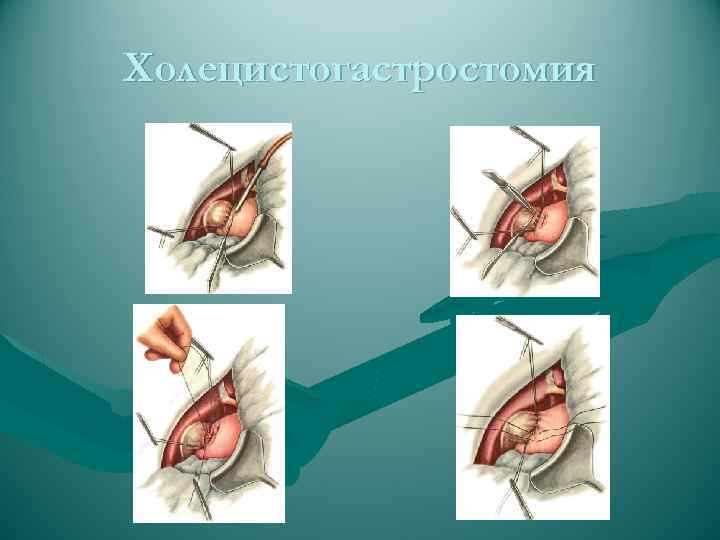

Холецистогастростомия

Холецистогастростомия